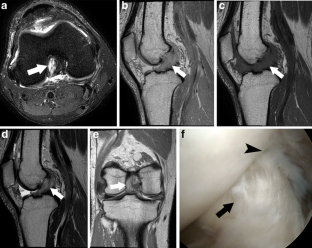

Fig. 1

Fig. 2

Fig. 3

Fig. 4